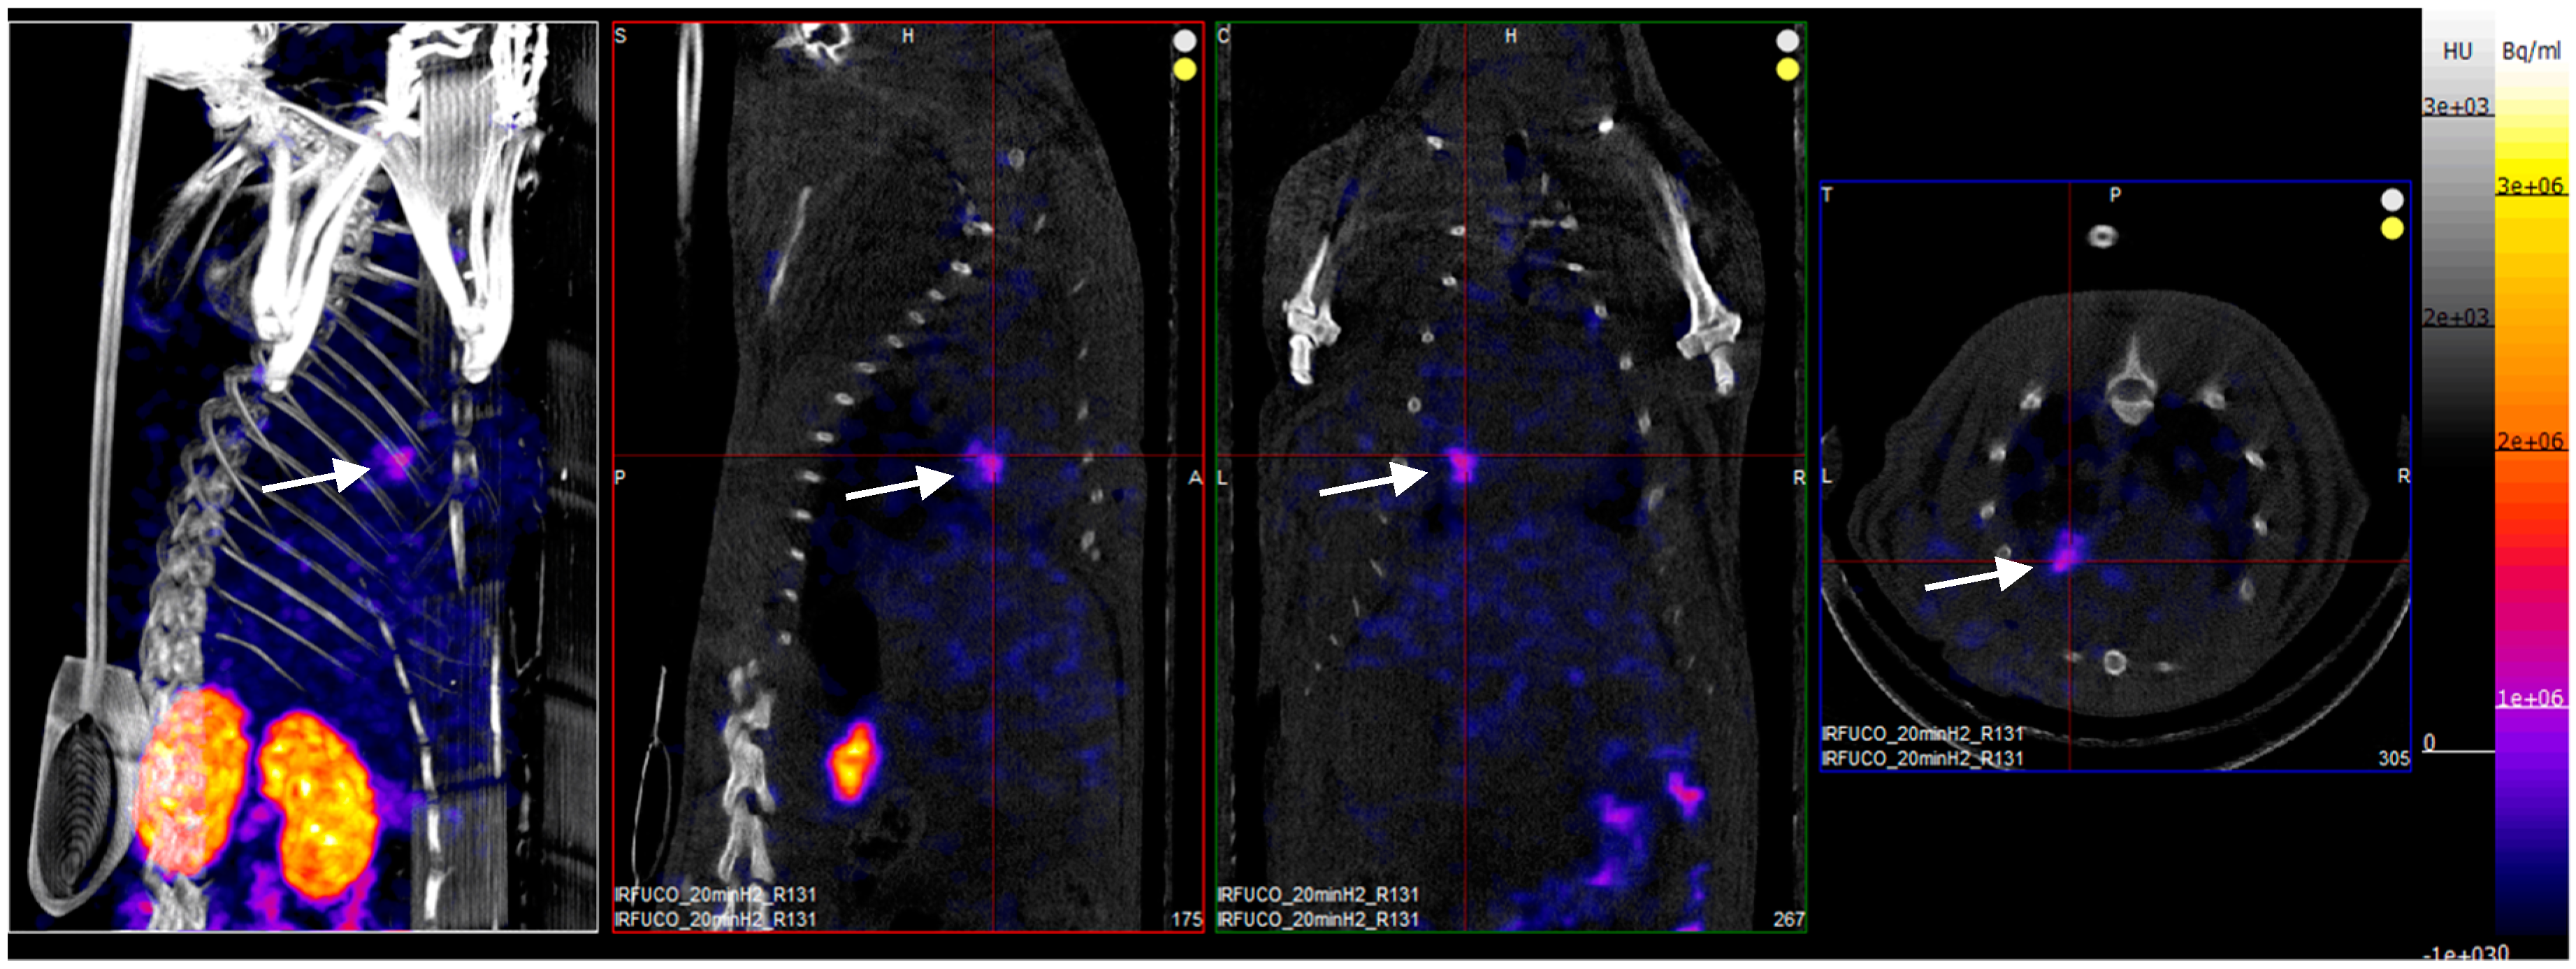

Four hours after reperfusion, a clear focal uptake of GMP grade LMW fucoidan labeled with 99mTc (Investigational Medicinal Product) had been detected in all animals confirming the presence of exposed P-selectin [18], either by endothelium cells or by activated platelets in the area of myocardial ischemia (Figure 3).

Figure 3.

SPECT/CT scans of an ischemia-reperfusion rat model acquired 2 h after intravenous injection of GMP grade LMW fucoidan labeled with 99mTc (Investigational Medicinal Product) (white arrows). Representative whole body SPECT/CT imaging: from left to right: 3D view, sagittal, coronal, and axial planes.